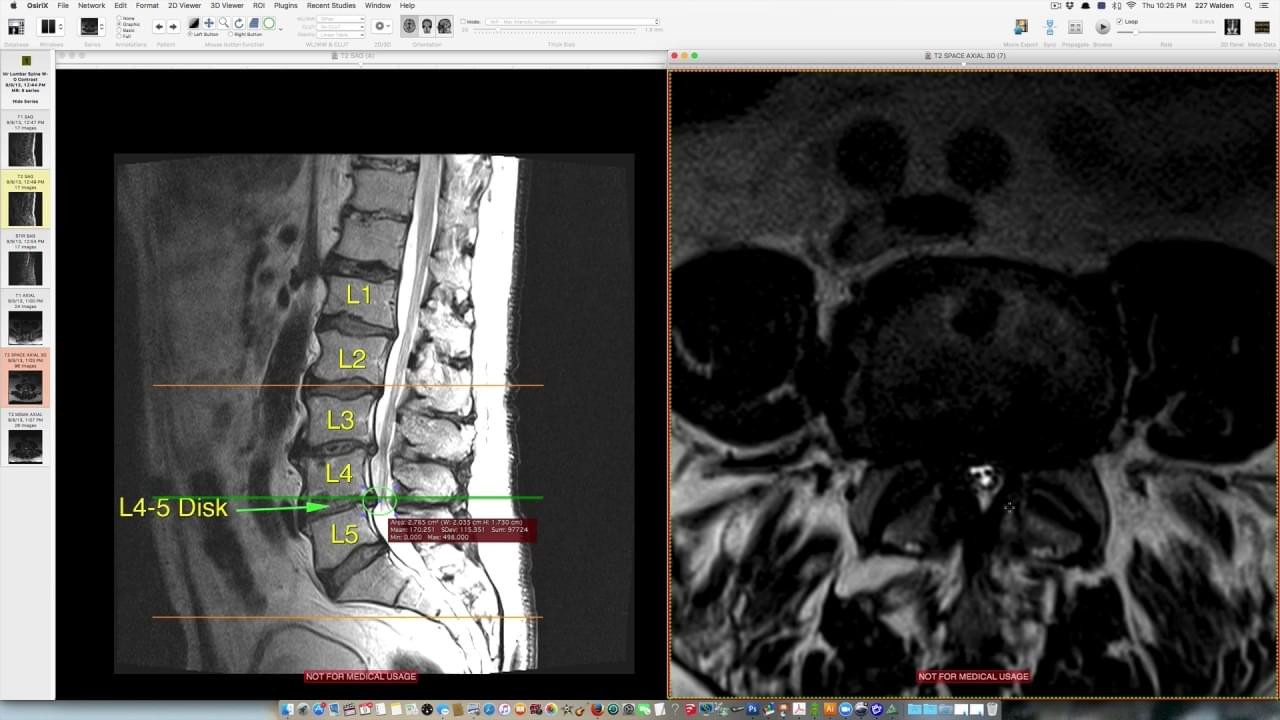

"Ich verstehe nicht. Bei der letzten Untersuchung hatten Sie durchgehend Schmerzen im unteren Rücken - und Ihre Röntgenbilder zeigten 3 degenerative Bandscheiben und schreckliche Wirbelsäulengesundheit..."

"Aber jetzt sehen Ihre Röntgenbilder unglaublich aus, und Sie können sich schmerzfrei bewegen - was ist passiert? Es sieht so aus, als hätten Sie Ihre Wirbelsäulenscheiben komplett geheilt!?"

"Wie sind also Ihre degenerativen Bandscheiben praktisch verschwunden, und Ihre Röntgenbilder zeigen, dass Ihre Wirbelsäule in nahezu perfektem Gesundheitszustand ist, wo Sie doch vor ein paar Monaten einige der schlimmsten degenerativen Bandscheiben hatten, die ich je gesehen habe? Ähm... keine Beleidigung..."